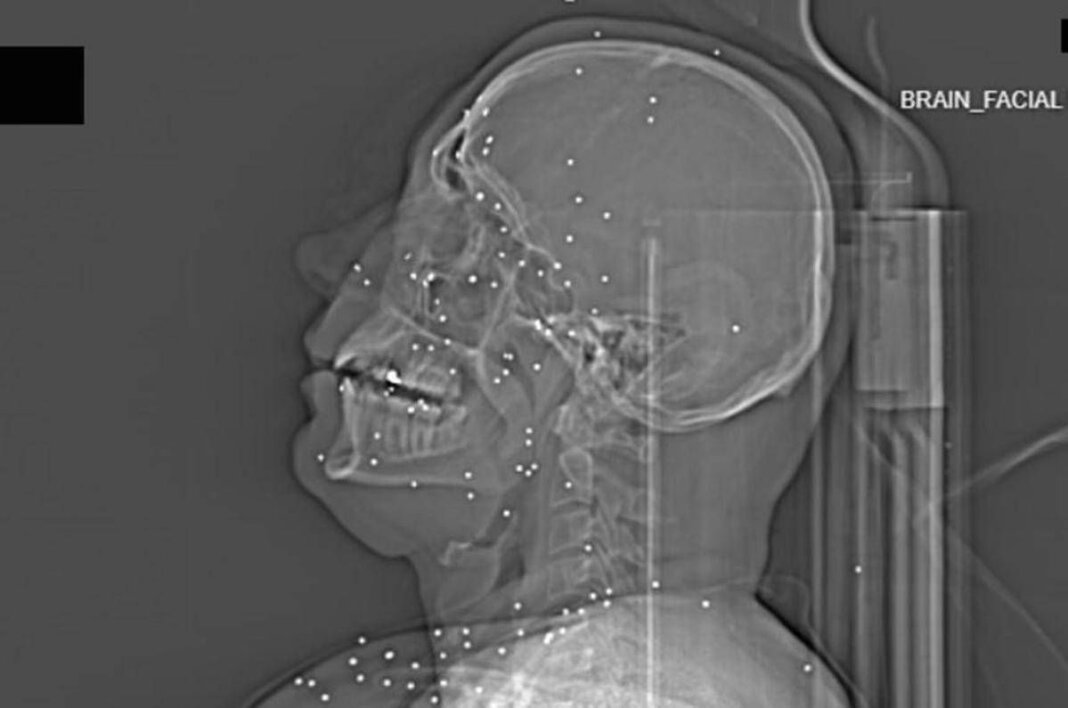

Il volto di Anahita – nome di fantasia, poco più che ventenne – appare come un cielo notturno attraversato da punti luminosi. Piccole sfere metalliche, da 2 a 5 millimetri, disseminate sul viso, nelle orbite oculari, persino nella massa scura del cervello. Sono proiettili “birdshot”, pallini da caccia sparati da un fucile a pompa. A distanza ravvicinata, spiegano gli esperti, non sono affatto “meno letali”: possono frantumare ossa, devastare tessuti molli, perforare facilmente un bulbo oculare. Anahita ha perso almeno un occhio, forse entrambi.

Quell’immagine non è un caso isolato. Fa parte di oltre 75 set di esami diagnostici provenienti da un singolo ospedale di una grande città iraniana, raccolti nel corso di una sola serata, durante la stretta repressiva di gennaio. Una concentrazione temporale che, già di per sé, racconta una dinamica da “mass casualty”, evento con numerose vittime simultanee, tipico degli scenari di guerra o dei grandi disastri.

Le valutazioni, condotte congiuntamente dal Guardian e dalla piattaforma di fact-checking Factnameh, sono state affidate a un panel indipendente di specialisti internazionali: medici d’urgenza, radiologi, esperti di trauma imaging e balistica. Un ex medico iraniano di pronto soccorso, anch’egli consultato, ha confermato la coerenza del software utilizzato per gli esami e l’assenza di segni di manomissione. Gli esperti precisano che, senza cartelle cliniche complete, non è possibile formulare diagnosi definitive sui singoli pazienti. Ma il quadro complessivo, spiegano, è inequivocabile.